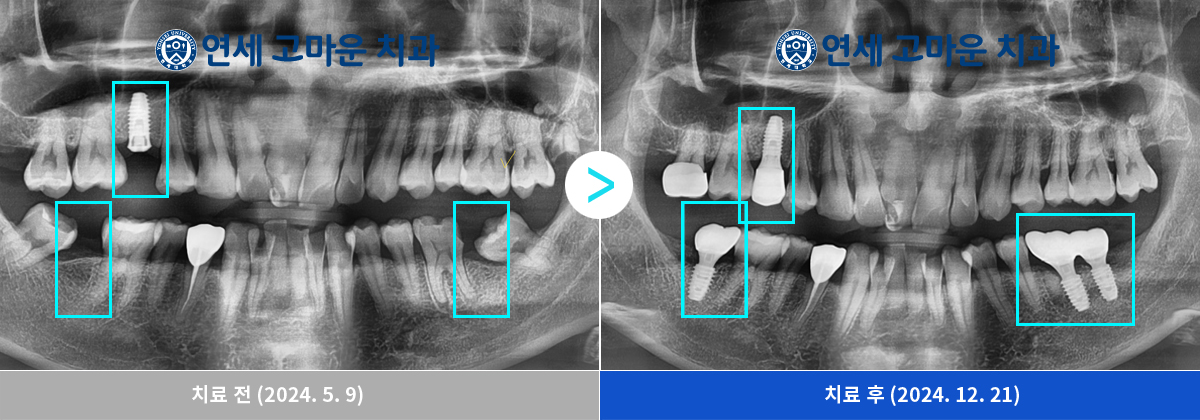

사랑니 발치 후 임플란트 4개 치료한 사례입니다.

상실된 치아를 오랫동안 방치한 탓에 사랑니가 누워서 교합이 불균형해지고 임플란트 보철 공간을 막고 있었기 때문에

사랑니 발치 후 임플란트 치료가 필요한 케이스였습니다.